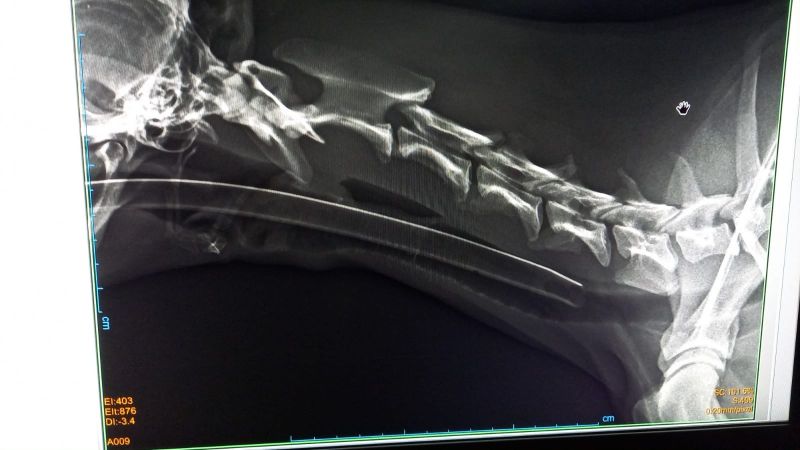

Pilar hat Esperanza bereits zu zwei Tierärzten in Zaragoza gebracht. Die Galga läuft seltsam und schrie regelrecht vor Schmerzen, insbesondere wenn sie am Hals angefasst wird. Es ist schrecklich, die arme Galga so leiden zu hören. Leider wissen wir aktuell noch nicht, was Esperanza hat. Beide Tierärzte haben unterschiedliche Vermutungen - es könnte eine alte Verletzung, aber auch ein Tumor an den Halswirbeln sein. Genauers kann nur ein MRT zeigen, welches auch in Spanien sehr kostenintensiv ist.

Update 14.07.: Nach diversen Untersuchungen und einer Nacht in der Tierklinik schließen die Tierärzte sowohl einen Tumor als auch einen Bandscheibenvorfall aus. Sie wollen aber noch die zerebrospinale Flüssigkeit untersuchen die sie schon, als Esperanza in Narkose war, abgenommen haben. Wir hoffen dass bald eine Diagnose gestellt werden und der süßen Maus geholfen werden kann.